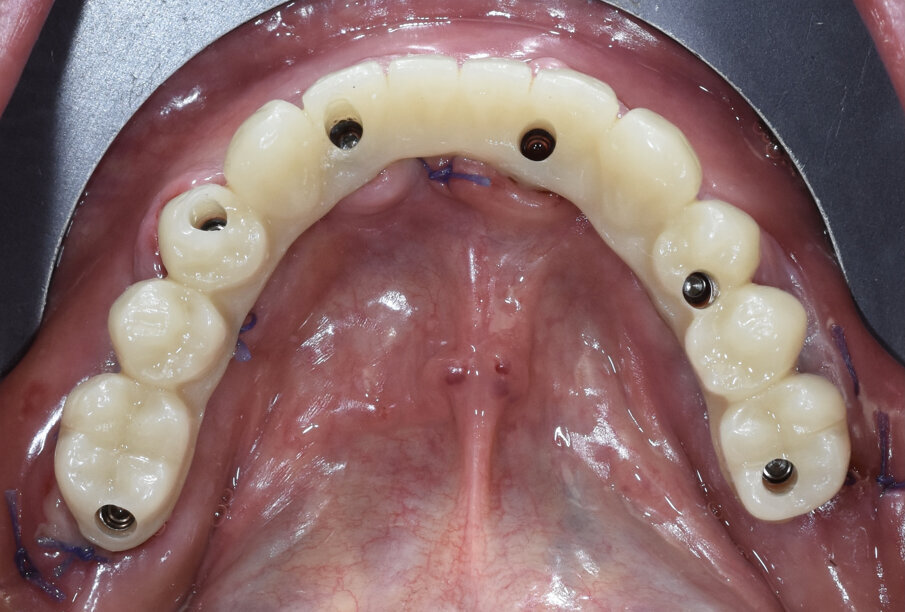

Paziente di sesso maschile di 73 anni, con anamnesi negativa per patologie di rilievo. All’esame clinico e radiografico si evidenzia nell’arcata inferiore la presenza di residui radicolari a supporto di un vecchio ponte, con attacchi per la stabilizzazione di una protesi scheletrata di tipo mobile. Prima di procedere alla fase chirurgica e di rimuovere lo scheletrito viene eseguita un impronta digitale con scanner (3Shape) in modo da registrare la dimensione verticale che verrà utilizzata come riferimento per la realizzazione del carico immediato. In sedazione cosciente e previa terapia antibiotica si procede alla rimozione dei residui radicolari, quindi si esegue una generosa osteotomia e si procede al posizionamento di numero 6 impianti assiali (AB Dental device) a esagono interno. Si esegue quindi la sutura dei lembi con vicryl 4/0 e si procede alla prese dell’impronta digitale utilizzando gli scan body come transfer (Figg. 1-11). I file in STL vengono inviati al laboratorio per la realizzazione della protesi provvisoria a carico immediato. Si applicano quindi le viti di guarigione. Dopo 72 ore si procede alla consegna del provvisorio che rimarrà in bocca per 4 mesi in attesa dell’osteointegrazione (Figg. 12-23).

Fig. 20 - Visione occlusale provvisorio.

Fig. 21 - Carico immediato.

Fig. 22 - Visione occlusale carico immediato.